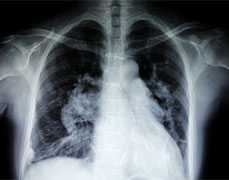

近日,我院胸心血管外科收治了一对患有先天性心脏病的孪生姐妹,并成功为她们完成手术。俩姐妹术后恢复正常,现已康复出院。 1年前,小鸿(姐姐...